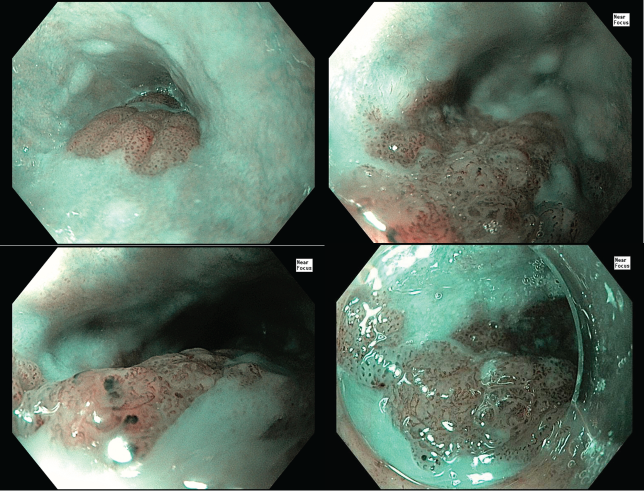

Quan sát với NBI

Dưới chế độ NBI, có thể quan sát thấy rõ vùng màu nâu, BC(+), vùng tổn thương đậm màu hơn so với niêm mạch lành, một dấu hiệu thường gặp trong ung thư biểu mô tế bào vảy thực quản. Tổn thương có đường ranh giới rõ ràng.

Theo phân loại JES, bác sĩ nhận thấy tổn thương có cấu trúc mạch máu type B1 (mạch máu dạng vòng bất thường, có đầy đủ 4 dấu hiệu: giãn, ngoằn ngoèo, đường kính không đều, hình dạng không đều -> mức độ xâm lấn dự đoán là nông EP/LPM) và một vùng nhỏ type B2 (mạch máu bất thường, ít tạo vòng -> mức độ xâm lấn nông MM/SM1).